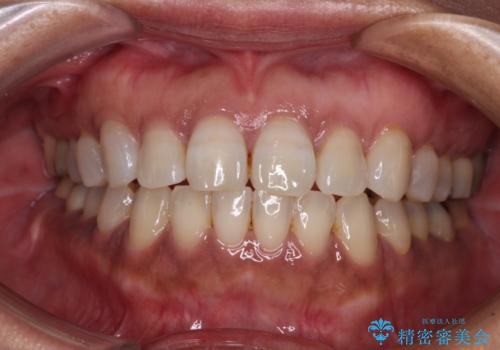

仮詰めのまま処置が進まないので転院 奥歯のむし歯治療

- 奥歯のむし歯処置を行っていたものの、しみて痛みが続く状態での経過観察が続いていたため、転院を希望して来院された患者様です。

仮詰めの状態が良くなかっただけで、むし歯が神経組織にまで及んでいることはなく、無事に治療を終えることができました。